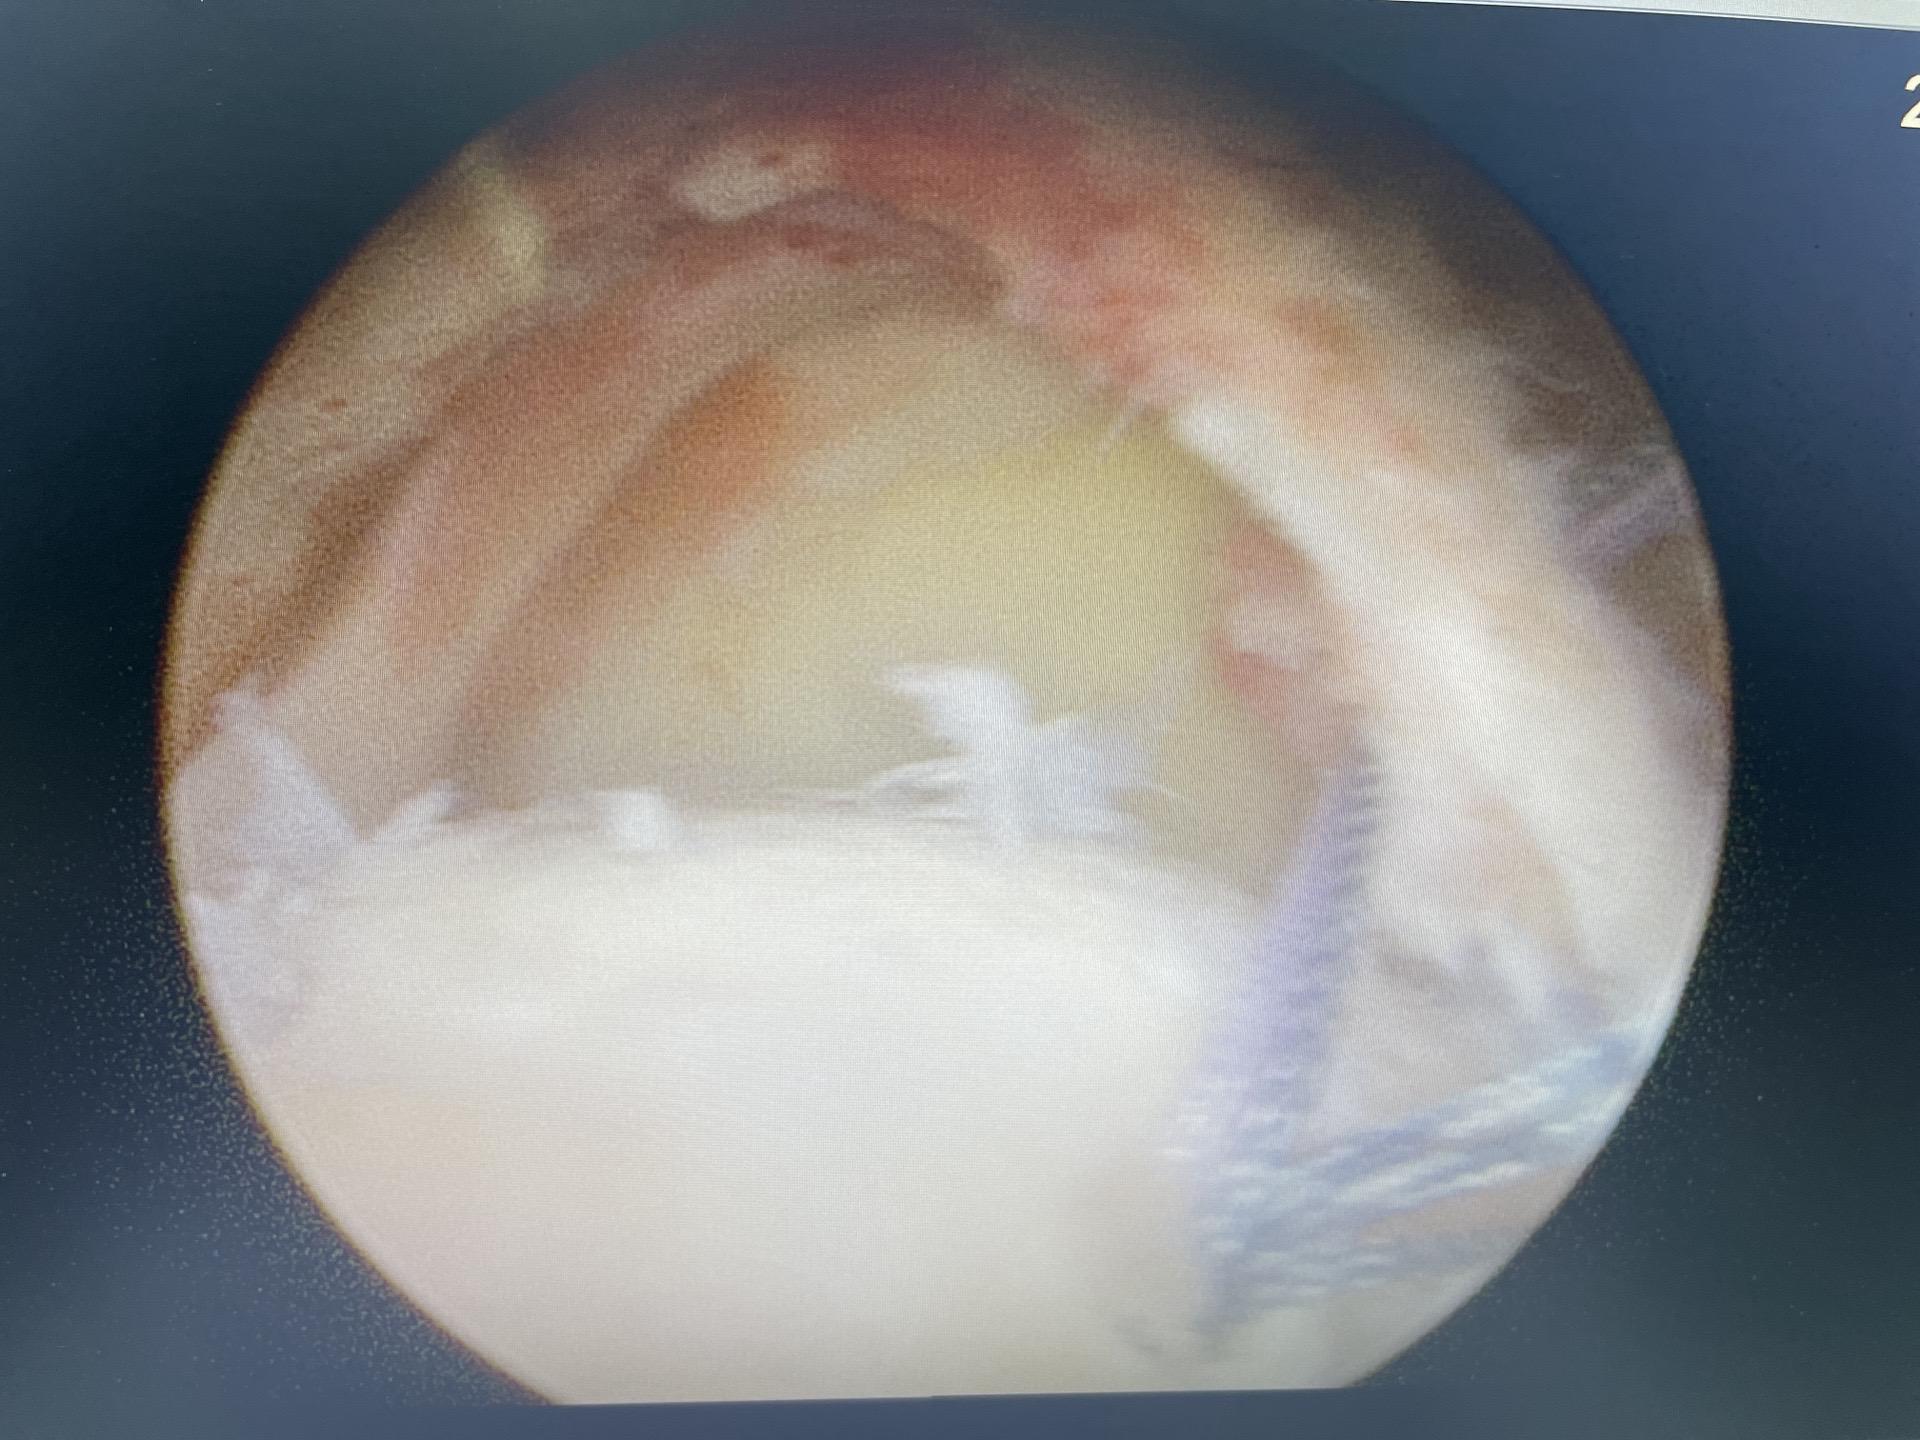

巨大肩袖撕裂修复。每一次置钉过线,每一次钳抓,每一次调整,都凝聚了我们的专业和努力,手术成功,患者安好,这是对术者最大的奖赏 肩袖撕裂 巨大肩袖撕裂 关节镜手术 关节镜微创手术